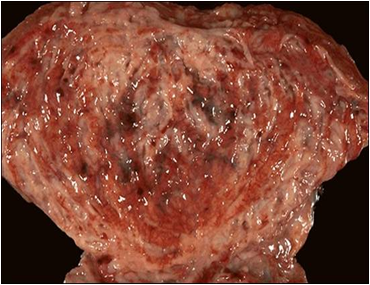

急性膀胱炎的病理变化主要表现为膀胱黏膜血管扩张、充血、上皮细胞肿胀、黏膜下组织充血、水肿及炎症细胞浸润,重者可有点状或片状出血,甚至黏膜溃疡。